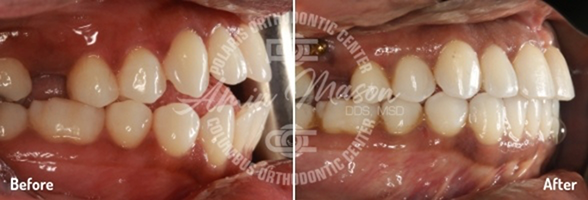

Case 7

An adult male patient presented to our office with a deep bite, crowding, and tooth wear. The patient exhibited class II molar occlusion, severe deep bite, and maxillary/mandibular crowding. The patient was treated with class II corrector and limited maxillary braces for a short time and was transitioned to Invisalign clear aligners. Patient achieved fantastic results and was very satisfied with the results. Treatment time: 22 months.